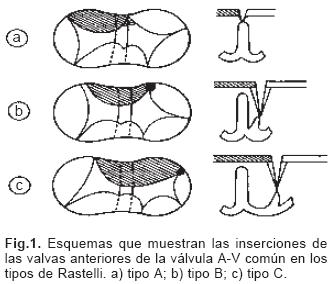

Se analizaron 70 corazones portadores de DSA–V pertenecientes a la colección patológica del Departamento de Embriología del Instituto Nacional de Cardiología "Ignacio Chávez". Se utilizó el método secuencial segmentario empleado en el diagnóstico anatómico de las cardiopatías congénitas.14,15 Se determinó el situs atrial , tipos y modos de conexión A–V y ventriculoarterial, morfología de los tabiques cardíacos y de las válvulas A–V, extensión del defecto septal A–V, alteraciones del esqueleto fibroso del corazón y anomalías asociadas; para determinar la geometría de los ventrículos se midieron las distancias entre la unión A–V y el ápex del corazón y entre éste y la válvula aórtica. Los corazones se clasificaron según el número de válvulas AV, además se utilizó la clasificación quirúrgica de Rastelli16 para determinar la inserción de la valva anterior izquierda o valva puente (Fig. 1). Se analizaron cortes histológicos de corazones embrionarios de pollo de los estadios 25 al 29 (4.5–6.5 días) de la clasificación de Hamburger y Hamilton17,18 que fueron correlacionados con los horizontes XIII al XVI (27–34 días) de Streeter19,20 del desarrollo del corazón humano, lo que sirvió de base para comparar las etapas embrionarias de la tabicación A–V con las alteraciones anatómicas de esta cardiopatía y con ello inferir su posible patogénesis.

De los sesenta y cinco corazones con válvula común en veinticinco se determinaron los tipos de la clasificación de Rastelli que fueron los siguientes: en once (44%) las valvas anterosuperiores derecha e izquierda se insertaron a través de sus cuerdas tendinosas sobre la cresta del tabique ventricular y la CIV se ubicó en los espacios intercordales (tipo A de Rastelli) (Figs. 1A y 5A). En un espécimen las valvas anterosu–periores izquierda (valva puente) y derecha se insertaron sobre la cara derecha del tabique ventricular por debajo de su cresta (Fig. 5B) y en otro dicha inserción se hizo en la parte superior del cuerpo de la trabécula septomarginal (Fig. 5C). En ocho corazones (32%) la inserción de esas valvas se estableció en un músculo papilar situado en la unión del tabique ventricular con la pared libre del ventrículo derecho y la valva anterosuperior izquierda pasó como puente por encima de la CIV (tipo B de Rastelli) (Figs. 1B y 5D) y en seis corazones (24%) la inserción de las valvas anterosuperior izquierda (valva puente) y derecha se insertaron en un músculo papilar de la pared libre del ventrículo derecho y esta valva se ubicó por encima de la CIV (tipo C de Rastelli) (Figs. 1C y 5E). En los cuarenta corazones restantes no fue posible determinar los tipos de Rastelli debido a que treinta y tres de ellos presentaron doble entrada ventricular (Fig. 6A) dos tuvieron modificaciones anatómicas generadas por la cirugía y cinco por presentar mutilaciones realizadas durante la necropsia. Los cinco especímenes con dos válvulas separadas tuvieron estructura trifoliada dentro de la unión A–V común (Figs. 3B y 6B); la válvula A–V izquierda mostró una valva lateral y dos septales anterior y posterior unidas a la cresta del tabique ventricular, lo que obliteró la CIV (Fig. 6C). La válvula A–V derecha mostró una valva septal displásica, una anterior y una posterior (Figs. 3B y 6B).

En cuanto a la clasificación de Rastelli16 existe en realidad un espectro de grados de inserción de las cuerdas tendinosas de la valva "puente" en la que los tipos A, B y C constituyen los sitios más frecuentes de esa inserción y se debe considerar la existencia de inserciones intermedias entre ellos como se evidencia en el presente trabajo. Los DSA–V presentes en la doble entrada ventricular ya sea izquierda, derecha o a ventrículoúnico,escapan a la clasificacióndeRastelliya que las valvas anterosuperior–izquierda (valva puente) y la anterosuperior derecha están contenidas en una sola cavidad ventricular. En las formas balanceadas de esta cardiopatía la válvula A–V común se conecta a partes iguales con ambos ventrículos. Las formas de dominancia ventricular se expresan cuando la válvula A–V común se conecta preponderantemente con un ventrículo, en la dominancia de tipo derecho el ventrículo izquierdo es pequeño, ya que posee menos superficie valvular, mientras que en la dominancia de tipo izquierdo es el ventrículo derecho el de menor tamaño. En este concepto se consideran las dobles entradas a ventrículo derecho o al izquierdo.30